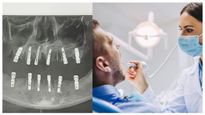

ஒரே நாளில் 23 பற்கள் பிடுங்கப்பட்ட சீன நபர் மாரடைப்பால் மரணம்!